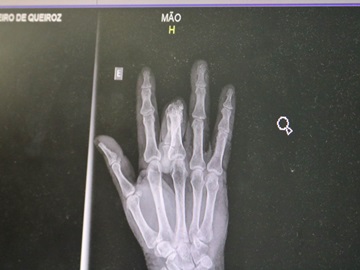

Visitante mineira reclama de atendimento do Hospital de Domingos MartinsImediatamente após o ocorrido, pela manhã, Maria procurou o Hospital Dr. Arthur Gerhardt (HMAG), de Domingos Martins. Lá chegando, foi feita uma radiografia, que constatou uma fissura no quarto dedo, e que logo foi diagnosticada como fratura da falange distal.

Ela recebeu medicação intravenosa para diminuir a dor que sentia. Após ser medicada, o médico fez um encaminhamento a paciente para que ela buscasse um ortopedista, a fim de que outras medidas adequadas à fratura fossem tomadas, uma vez que o Hospital não possui a especialidade de ortopedia.